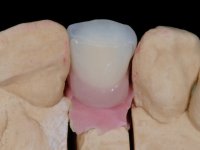

Treatment began with re-preparation of the cast post and core, with the purpose of placing the cervical finishing lines with an intra-sulcular location and simultaneously making a suitable temporary crown. With a very simple orthodontic treatment, the diastema was closed between the upper central incisors, and this position was stabilized with a wire placed on the palatal surface of the central, functioning as containment. Later, a slow orthodontic traction of tooth 2.2 was attempted, in order to reduce, although very slightly, the vertical bone loss in this area. At the end of the traction, tooth 2.2 was extracted and the area was provisionally rehabilitated with a composite resin crown bonded to the adjacent teeth. A dental implant was placed in the area of tooth 2.2 and the temporary crown was again bonded to resin, provisionally rehabilitating the patient during osseointegration. In tooth 1.3 a gingivectomy with an electric scalpel was performed, with the intention of raising the cervical level of 1.3 achieving greater harmony with tooth 2.3. Stabilized soft tissues were impressed using the open tray technique with putty and light addition silicones. Collection of the color of both the dental component and soft tissues was done by the ceramist in the office. In the laboratory, the impressions were transferred to plaster and gave origin to work models that were properly analyzed. It was decided to assemble a metal-ceramic abutment screwed onto the implant. This abutment was cast with a noble alloy and subsequently coated with coronary and gingival ceramics. Due to the inclination of the implant, the screwing inevitably conditioned the exit of the screw hole through the vestibular surface. In order to conceal this situation, the design of the abutment has already been conceived with the intention of accommodating on the vestibular surface the bonding of a feldspathic veneer. This abutment was tested in the mouth and adjustments were made in the gingival ceramic component. Its adaptation to the soft tissues was done in a subtractive way, with a drill, as well as additive, adding resin composed of gingival tonality.

This addition of resin would guide the ceramist in the final placement of the gingival tonality ceramic. The crown that would rehabilitate tooth 1.3 was cemented in this test session with glass ionomer cement, reinforced with composite resin. Once the laboratory work was finished on the veneer for tooth 1.2, the abutment, and the veneer for the implant, this was bonded in the mouth, after placement of the absolute insulation. The work completely satisfied the patient. For eight years, the patient had periodical check-ups, and was pleased with the treatment, but also began to show interest in an aesthetical intervention on the upper central incisors. Once the second phase of our intervention was decided, dental preparation of teeth 1.1 and 2.1 was performed for the placement of two feldspathic veneers. Particular care was taken in the distal inter-proximal preparation adjacent to the abutment of the implant.